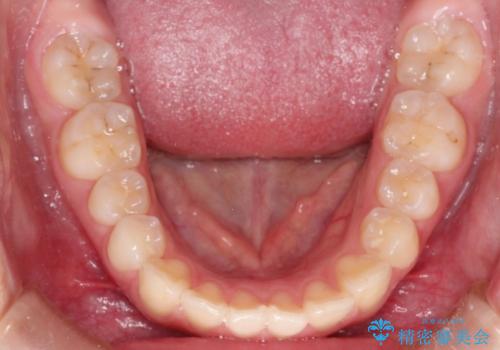

- 前歯が出ているのを主訴に来院されました。

上の前歯が前方に傾斜しており、上の前歯と下の前歯が接触していない状態でした。

上の奥歯を後方に移動させて、前歯を引っ込める計画としました。